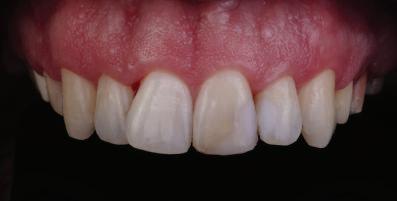

Пациентът постъпи в клиниката с молба за тотална рехабилитация на усмивката. Той не харесваше централ ните си резци, които според него бяха твърде къси и квадратни. Имаше раз стояние от медиално и дистално на латералните му резци. Друго сериоз но оплакване бе свързано с металоке рамичната корона на зъб 12, която бе жълтеникава и неестетична, като цяло не харесваше вида на венците си и както самият той се изразяваше, „вижда се прекалено много от венците при усмивка“.

След диагностиката бяха направени екстра- и интраорални снимки, както и рентгенографии; професионалното почистване бе от изключителна важ ност, бяха дадени и инструкции за лич на орална хигиена. Бе направено интра орално сканиране с Medit i500. Цялата тази информация бе използ вана в приложението Smilecloud за 2D биометричен дизайн. В приложението са налични естест вени форми на зъбите и щом бяха под брани зъби и бе направен дизайн

библиотеката на Exocad. Струва си да се отбележи, че 2D дизайнът от Smile Cloud бе спазен до последния детайл в Exocad smile creator с цел да се създаде 3D obj файл със зъбните форми. След като естетичният дизайн бе готов в model creator модула на Exocad, адитивен 3D мок-ъп модел бе експорти ран и принтиран от принтер Formlabs 3. Моделът бе използван за направата на силиконов водач, за да се изготви мо тивационен мок-ъп в устата на паци ента и да се оценят естетичните па раметри. След като пациентът одобри вида на усмивката си, мок-ъпът бе използван за финализиране дизайна на усмивка та. Мок-ъпът бе използван също така като водач по време на мекотъканна та хирургия, както и при препарация на зъбите.

Препарираните зъби бяха импорти рани в Exocad и насложени върху ес тествените форми от биометричния дизайн, като така стана ясно дали зъ бите са били препарирани коректно. По този начин зъболекарят и зъботехни кът работят в една и съща екосистема и резултатът е оптимален. С короната се справихме чрез диги тална редукция на циркония в Exocad, като по този начин на практика създа дохме циркониево кепе, след което про изведохме фасета от IPS Empress Cad Multi. Кепето от Katana Zirconia на зъб 12 с букално послойно нанесена керами ка бе фрезовано (послойното нанасяне бе направено, за да се подобри връзката и да се осигури адхезивно циментиране на фасетата към циркониевото кепе, както и за да се напасне цветът към този на съседните зъби). При първото сканиране регистрирах ме цялата горна зъбна дъга, така че, ко гато се наложи да сканираме повторно, бе изтрит и сканиран наново само зъб 12, тъй като венците не бяха отдръп нати при второто сканиране.

НА

рентгенографии. Инициална терапия и професионално почистване. Интраорално сканиране с цел диги тално планиране. Регистрация и 3D ориентиране на ок лузалната равнина на горна и долна челюст в пространството. 2D дигитално планиране и дизайн на усмивката посредством приложение то Smile Cloud. 3D дигитално планиране и дизайн на функционалните и естетичните па раметри. 3D дигитален дизайн и адитивен мокъп на горна челюст. 3D принтиране и мок-ъп модели. Мотивационен мок-ъп. Фини корекции за постигане на фи налния дизайн. Мекотъканна хирургия с мок-ъпа като водач Препарация през мок-ъпа, използвай ки дизайна като водач за финалната препарация в Exocad. Циркониево кепе ще бъде циментира но с цел адхезивно залепяне на фасе та на края. Кепето има същия цвят като този на съседните зъби, за да може фасетата да се впише перфект но в цялостната усмивка. Изработване на 12 IPS Empress Cad Multi фасети с послойно нанесена ке ТОТАЛНА РЕХАБИЛИТАЦИЯ НА УСМИВКАТА С ИЗЦЯЛО ДИГИТАЛЕН ПРОТОКОЛ Д-р Калин Маринов и зт. Стефан Петров рамика букално върху зъбните препа рации и върху първичното циркони ево кепе (има възможност за ецване и адхезивно

Една седмица след препарацията на зъбите и циментирането на цирко ниевото кепе бяха изработени 12 IPS Empress Cad Multi фасети. Макро- и микротекстурата на фасе тите бяха направени на ръка, след кое то бяха нанесени 3D характеризации с боички, а полирането отново бе напра вено ръчно, за да им се придаде естест вен и естетичен вид. Предизвикателството тук беше короната да има същите оптични характеристики като тези на остана лите зъби при естествена светлина, през поляризационен и флуоресцентен филтър. 3D принтерът бе Fromlabs, софтуерът за фрезоване – Mill Box, а фрез апаратът –imes icore CORiTEC 350i. В крайна сметка постигнахме ес тествен вид на усмивката с натурал на зъбна морфология при изцяло диги тален протокол, при който дизайнът бе направен първоначално и през всич ки етапи на лечението се придържахме към него до самия край Излишно е да отбелязваме, че всички сме удовлетворени от постигнатото! Преди След Победител в категория „Клиничен случай с изцяло дигитален протокол“ в конкурса „Усмивка на годината 2022“

11Dental Tribune Bulgarian Edition / октомври 2022 г. Преди лечението Фиг. 1 Фиг. 2 Фиг. 3 Фиг. 4 Фиг. 5 Фиг. 6 Фиг. 7 Фиг. 9 Фиг. 10 Фиг. 11 Фиг. 8 Фиг. 12 Фиг. 13

12 Dental Tribune Bulgarian Edition / октомври 2022 г. По време на лечението Фиг. 14 Фиг. 16 Фиг. 20 Фиг. 23 Фиг. 21 Фиг. 24 Фиг. 26 Фиг. 28 Фиг. 31 Фиг. 34 Фиг. 29 Фиг. 32 Фиг. 35 Фиг. 30 Фиг. 33 Фиг. 36 Фиг. 27 Фиг. 22 Фиг. 25 Фиг. 17 Фиг. 18 Фиг. 19 Фиг. 15

13Dental Tribune Bulgarian Edition / октомври 2022 г. След лечението За авторите: Д-р Калин Маринов е специалист в областта на имплантологията, протетиката и естетичната хирургия. Завършил е дентална медици на в София през 2012 г. През 2014 г. основава Sky Dental Clinic. Бил е на обмен ни начала в катедра „Протетика“ на Университета по дентална медицина във Фрайбург, Германия. Живял е и е практикувал в Мелбърн, Австралия, и е посеща вал курсове и лекции в Италия, Швейцария, Германия с насоченост в естетич ната хирургия и имплантология, както и тоталната рехабилитация на устна та кухина чрез импланти. Зт. Стефан Петров основава собствена лаборатория през 2006 г. Официален демонстратор на GC за България, като от 2015 г. е KOL за Източна Европа. Инструктор е на Straumann за България. Лаборатория та му има сертификат за пилотна лаборатория на Micerium – Италия. Носител е на множество награди в денталния конкурс „Усмивка на годината”. Носител е на награда CERAMISTS MASTER CUP с д-р Софиен Риахи в престижния международен конгрес CERAMISTS – NO LIMITS 2015 г. Изнася лекции и провежда курсове в редица европейски страни. Фиг. 37 Фиг. 40 Фиг. 43 Фиг. 45 Фиг. 47 Фиг. 50 Фиг. 48 Фиг. 49 Фиг. 41 Фиг. 44 Фиг. 46 Фиг. 42 Фиг. 38 Фиг. 39